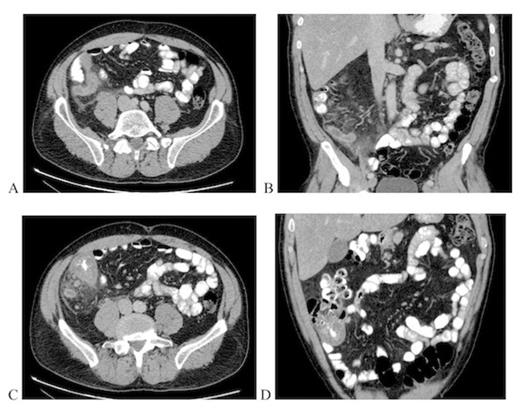

Upon assessment in the emergency department, he did not appear ill and was afebrile. Abdominal examination revealed localized guarding at McBurney's point. His white blood cell count was 12.0 x 109 cells/L. Computed tomography abdomen and pelvis revealed a markedly dilated appendix measuring 1.3 cm with fat stranding and enlarged lymph nodes. The caecal wall appeared irregular and thickened (Figure 1). The clinical impression at the time was consistent with an acute appendicitis with a potential caecal neoplasm.

Computed tomography images obtained preoperatively. Axial (a) and coronal (b) views of inflamed appendix. Axial (c) and coronal (d) views of thickened caecal wall and adenopathy.